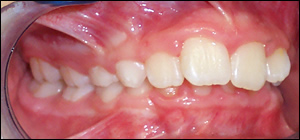

Fig 1: A 9 year old boy presented with a deep overbite and a retruded mandible. An analysis revealed that the deep overbite was retarding the downward and foward growth of the mandible (lower jaw).